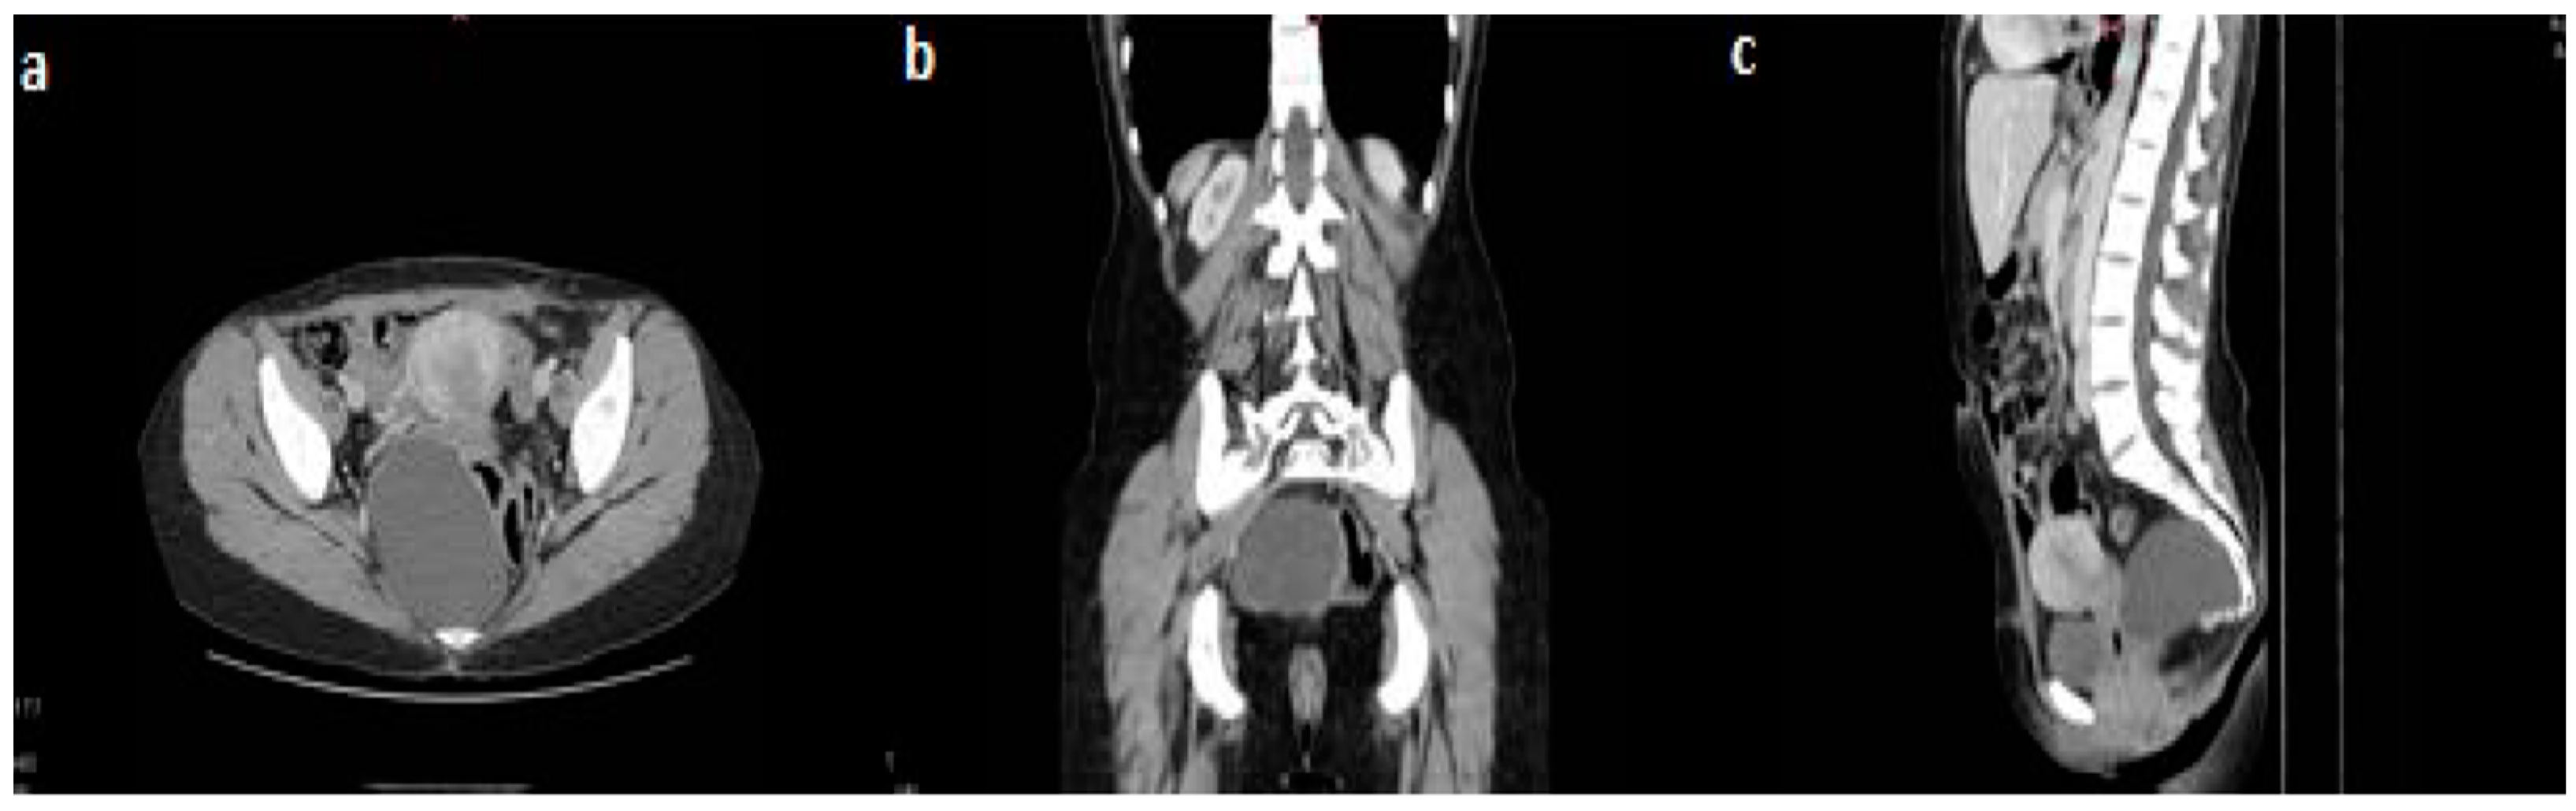

2. Case Presentation